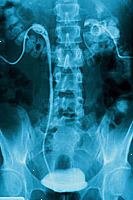

Μια ενδοφλέβια pyelogram, που ονομάζεται επίσης ενδοφλέβια ουρογραφία, είναι ένα διαγνωστικό ακτίνων Χ των νεφρών, ουρητήρων, ουροδόχου κύστης και. Όταν ένα σκιαγραφικό εγχέεται ενδοφλεβίως (IV), το ουροποιητικό σύστημα θα εμφανιστούν πολύ καθαρά, η οποία δεν παρατηρείται σε κανονικό ακτινογραφίες. Μια ενδοφλέβια pyelogram μπορεί να γίνει για πολλούς λόγους, συμπεριλαμβανομένων των εξής:

Καθώς το σκιαγραφικό κινείται εντός και διαμέσου των νεφρών, ουρητήρων, ουροδόχου κύστης και, ακτίνες Χ λαμβάνονται σε σύντομα χρονικά διαστήματα μπορεί να συλλάβει την κίνηση του. Μια καθυστέρηση στην σκιαγραφικό κινείται μέσω του ουροποιητικού συστήματος μπορεί να υποδεικνύει μια απόφραξη (φράξιμο) στη ροή του αίματος του νεφρού ή κακή λειτουργία των νεφρών.

Ένας ακτινολόγος μπορεί στη συνέχεια να αξιολογήσει τη λειτουργία και την ανίχνευση ανωμαλιών του ουροποιητικού συστήματος. Η δοκιμή αυτή είναι συνήθως καταδικάζεται ως μια από τις πρώτες δοκιμές σε περιπτώσεις υποψίας νεφρική νόσο ή παθήσεις του ουροποιητικού συστήματος.